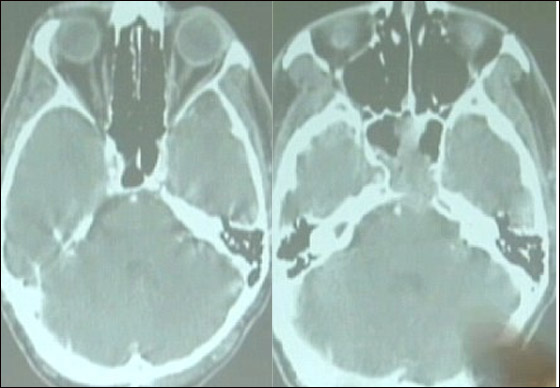

وعلى أساس حجم الورم الذي طال أجزاء من المخ قال الأطباء إن فرصة بيرجر في الحياة ستكون ثلاثة أو أربع سنوات ونسبة نجاته لن تزيد عن 10 %، بحسب صحيفة "ديلي ميل" البريطانية. وخضع بيرجر لعلاج مكثف من الإشعاع والكيماوي الذي ساعد في انكماش الورم، لكنه يعتقد أن العلاج لم يكن السبب الوحيد في مواجهه المرض. ويقول بيرجر لشبكة تلفزيون "إيه بي سي" الأمريكية: "لقد استيقظت في منتصف الليل وشعرت كأن الله يطلب مني أن أتوقف عن تعاطي العلاج وأخبرني بأن المرض قد انتهى".